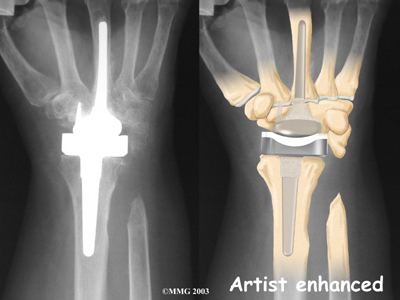

Modern artificial wrist joints are made of metal and plastic. The part that fits against the end of the radius bone of the forearm is called the radial component. It is made up of two pieces. A flat metal piece is placed on the front part of the radius. It has a stem that attaches down into the canal of the bone. A plastic cup fits onto the metal piece, forming a socket for the artificial wrist joint.

The part that replaces the small wrist bones is called the distal component. This piece is made completely of metal. It is globe shaped to fit into the plastic socket on the end of the radius. The metal distal component is attached by two metal stems that fit into the hollow bone marrow cavities of the carpal and metacarpal bones of the hand.

The plastic used in artificial joints is tough and slick. It allows the two pieces of the new joint to glide easily against each other as you move your wrist. The ball and socket allow movement of the wrist in all directions.

The surgeon will take some time to get the stems to fit tightly. The joint is put in place and tested through its range of motion to make sure it moves correctly. Once the surgeon is satisfied with the fit, the stems of each metal implant are:

Cemented into Place